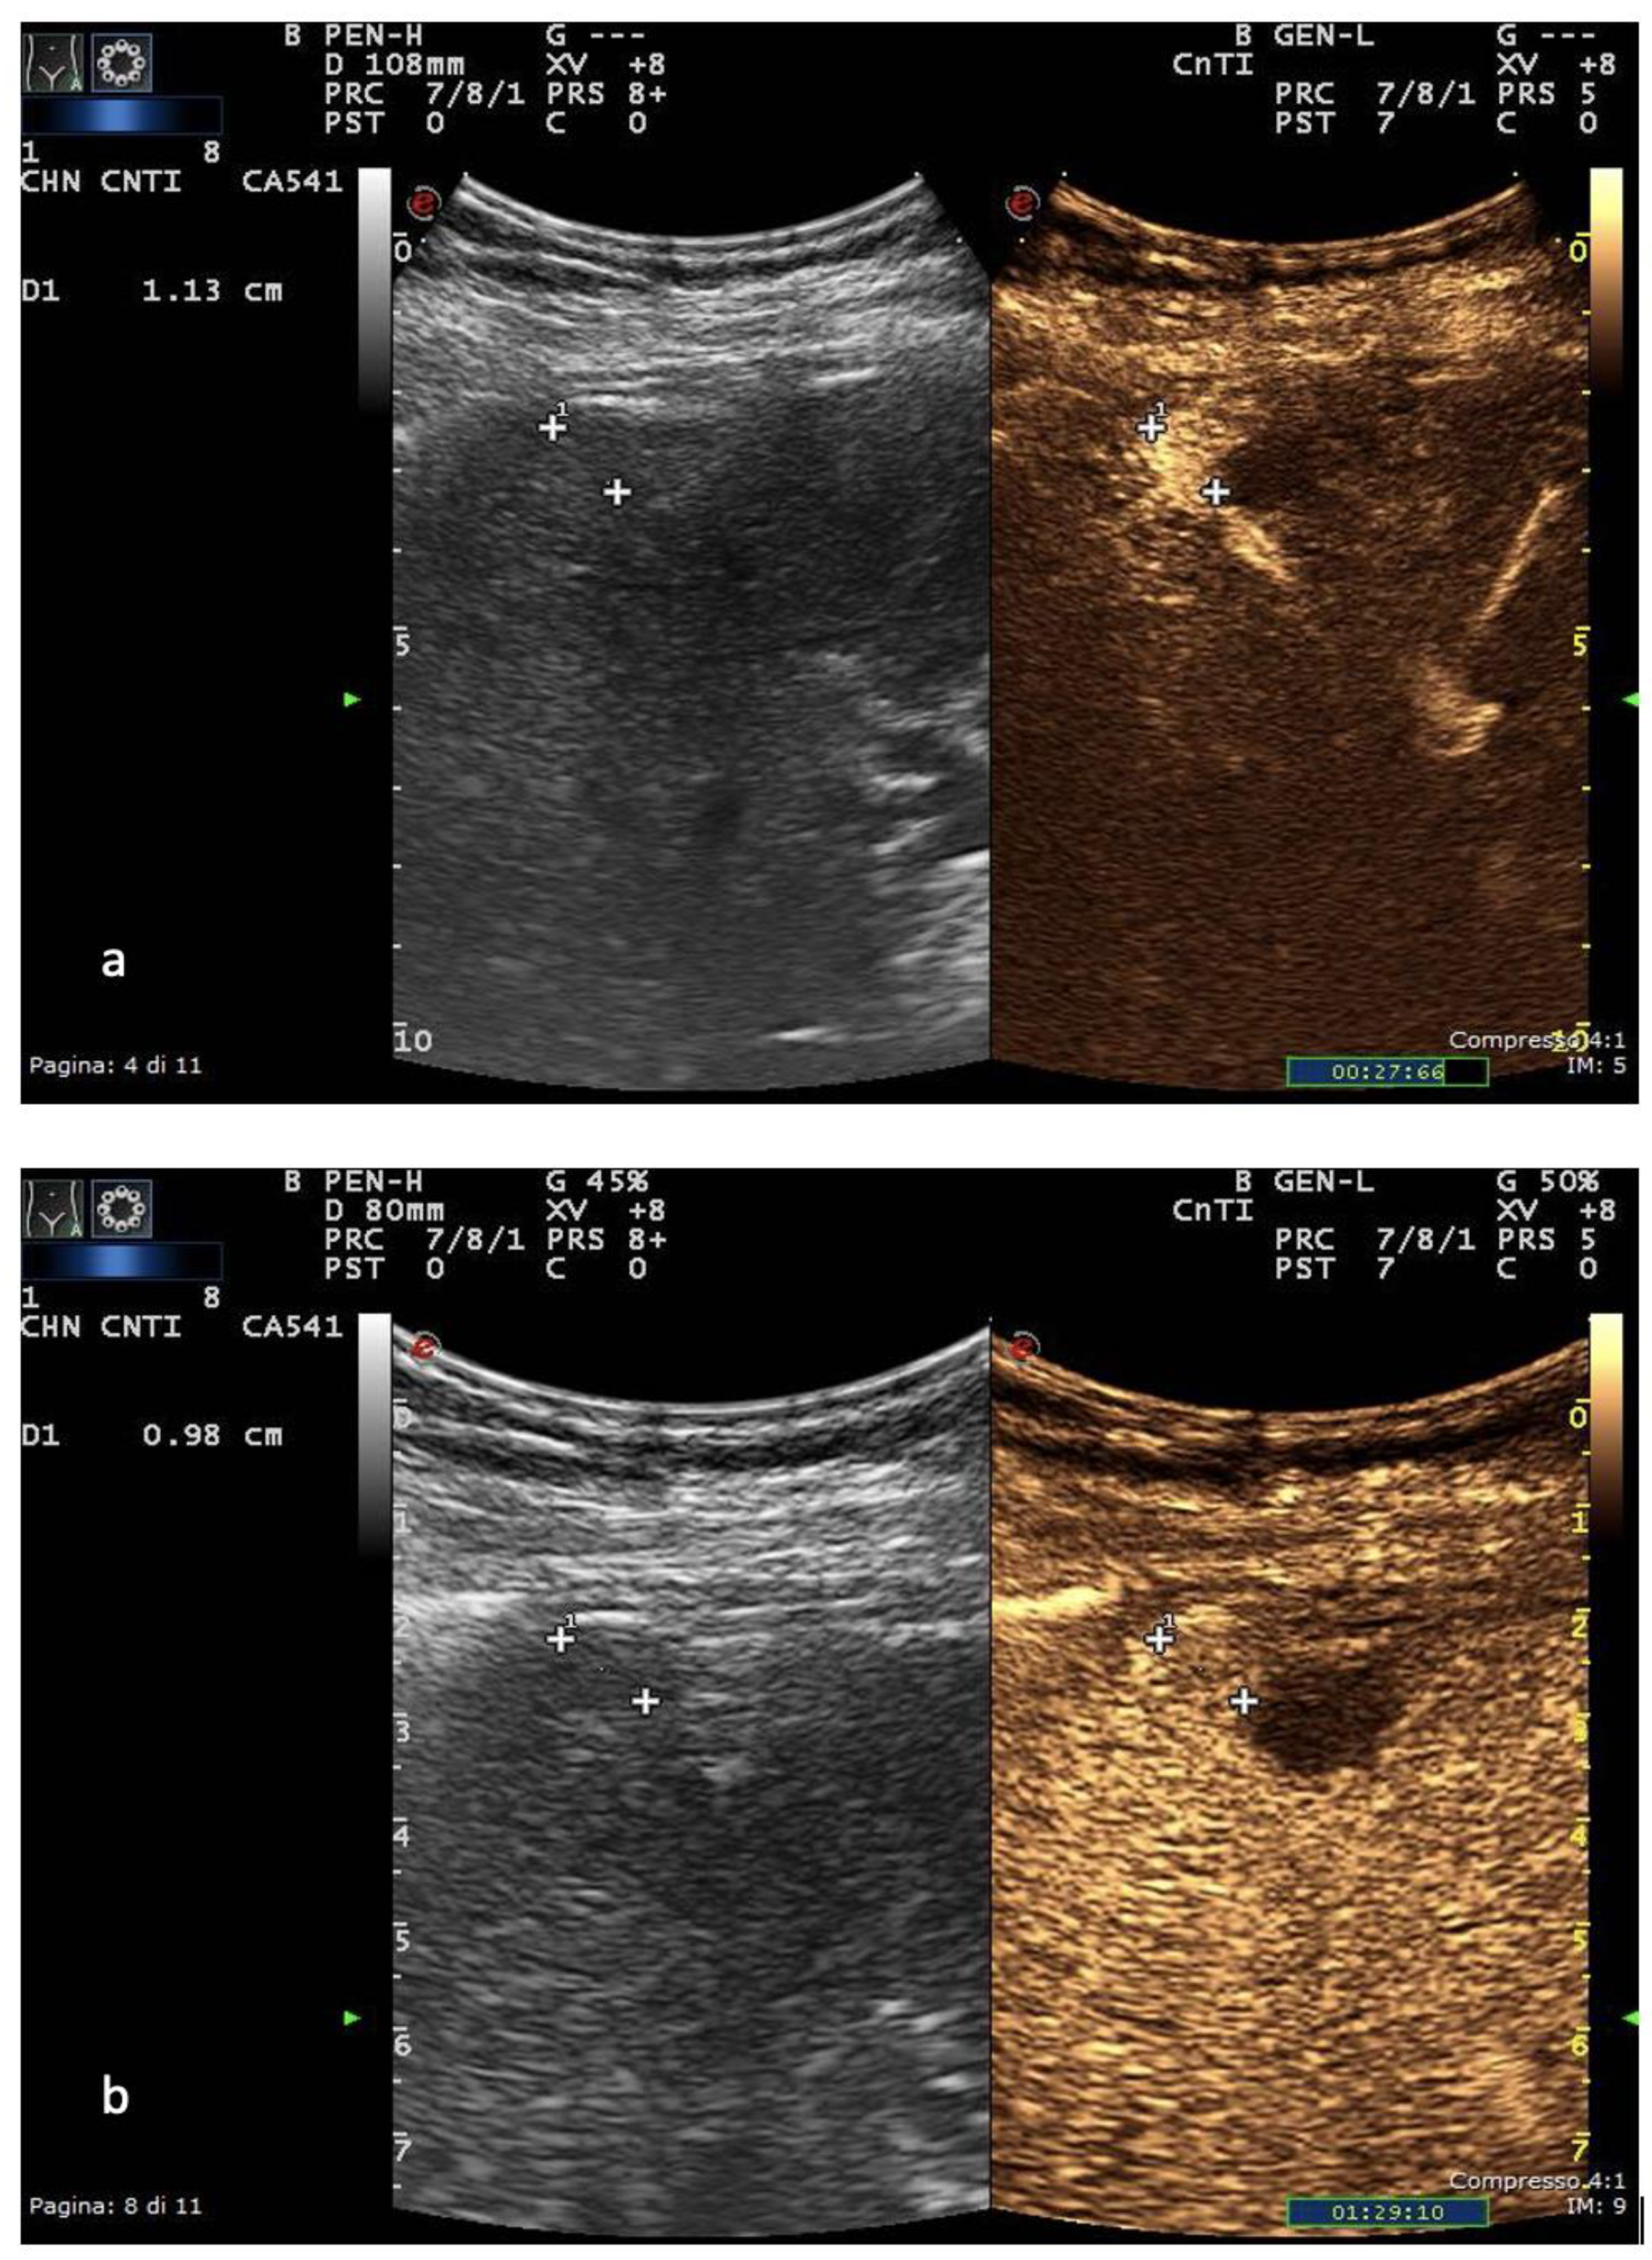

2. Ultrasound

- Eisenbrey, J.R.; Gabriel, H.; Savsani, E.; Lyshchik, A. Contrast-enhanced ultrasound (CEUS) in HCC diagnosis and assessment of tumor response to locoregional therapies. Abdom. Imaging 2021, 46, 3579–3595. [Google Scholar] [CrossRef]

- Bartolotta, T.V.; Taibbi, A.; Midiri, M.; Lagalla, R. Contrast-enhanced ultrasound of hepatocellular carcinoma: Where do we stand? Ultrasonography 2019, 38, 200–214. [Google Scholar] [CrossRef] [PubMed]

- Beckmann, S.; Simanowski, J.H. Update in Contrast-Enhanced Ultrasound. Visc. Med. 2020, 36, 476–486. [Google Scholar] [CrossRef]

- Dietrich, C.F.; Nolsøe, C.P.; Barr, R.G.; Berzigotti, A.; Burns, P.N.; Cantisani, V.; Chammas, M.C.; Chaubal, N.; Choi, B.I.; Clevert, D.-A.; et al. Guidelines and Good Clinical Practice Recommendations for Contrast-Enhanced Ultrasound (CEUS) in the Liver–Update 2020 WFUMB in Cooperation with EFSUMB, AFSUMB, AIUM, and FLAUS. Ultrasound Med. Biol. 2020, 46, 2579–2604. [Google Scholar] [CrossRef]

- Yang, H.K.; Burns, P.N.; Jang, H.-J.; Kono, Y.; Khalili, K.; Wilson, S.R.; Kim, T.K. Contrast-enhanced ultrasound approach to the diagnosis of focal liver lesions: The importance of washout. Ultrasonography 2019, 38, 289–301. [Google Scholar] [CrossRef] [PubMed]

- Bartolotta, T.V.; Terranova, M.C.; Gagliardo, C.; Taibbi, A. CEUS LI-RADS: A pictorial review. Insights Imaging 2020, 11, 9. [Google Scholar] [CrossRef]